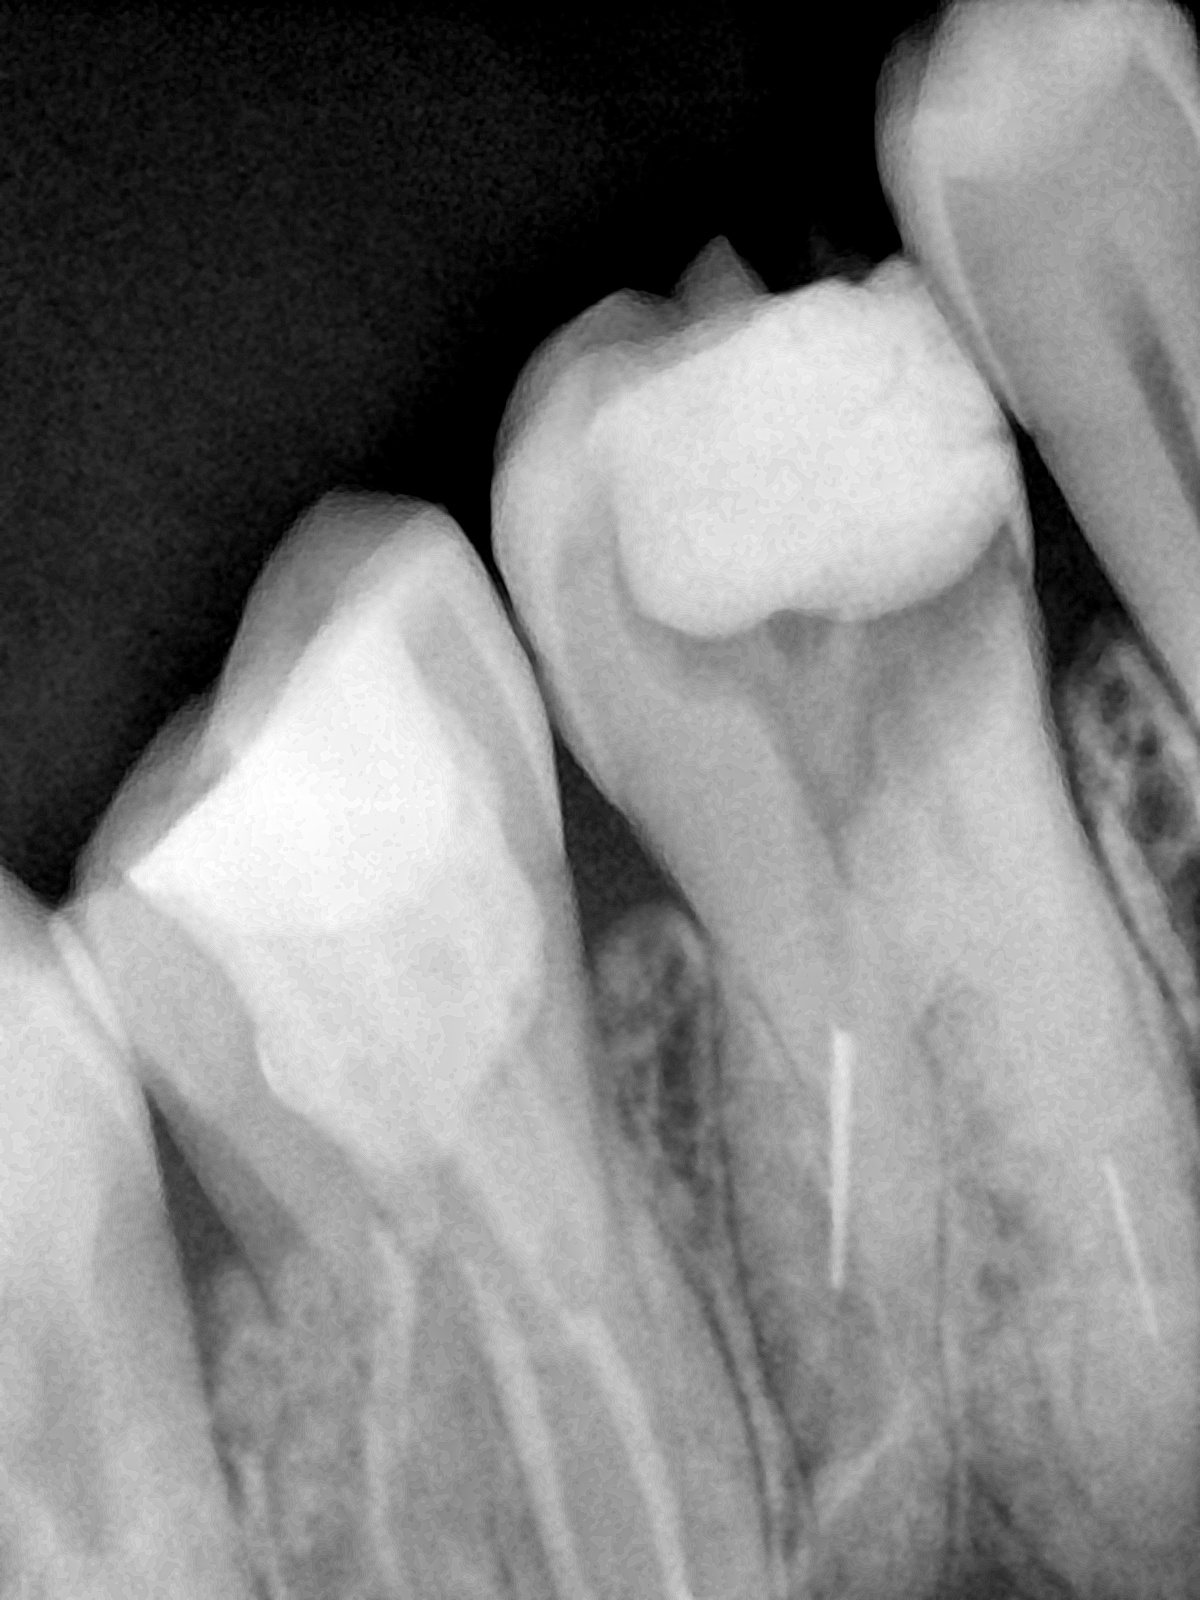

CR/DR 牙齿分割阶段记录

当前进展

- 完成了 CR/DR 牙齿相关分割训练

- 当前结果已经达到阶段预期,但仍有细节问题需要继续处理

相关测试

遇到的问题

- 训练过程中出现过 mask 下移问题

- 部分结果会出现 box 填充异常

- mask 边缘仍然有比较明显的锯齿感

第二版算法问题测试